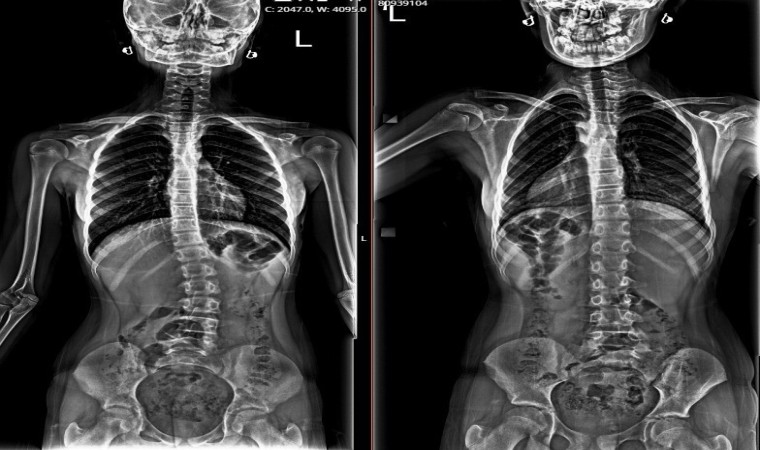

“Melis, bir buçuk yıldır dış hekim tarafından skolyoz takipli, bize kontrole geldi. Değerlendirdiğimiz zaman; 26 derece skolyoz olduğunu tespit ettik, nedenini araştırırken pelvik dengesizlik dediğimiz leğen kemiğinde bir dengesizlik olduğunu değerlendirdik. Yaptığımız klinik değerlendirmeler ve fizik muayene sonucu; bacakta eşitsizliğin dengelendiği zaman, skolyozun fayda görebileceğini öngördük. Yaklaşık 1,5 cm yükseklik ayağına uygulayarak tekrar röntgenini çektiğimizde, skolyoz derecesinin sıfıra yakın bir dereceye indiğini gördük. Sonrasında Melis’e tabanlık verdik, herhangi bir korse ya da cerrahi tedavi olmadan derecesini bu şekilde takip etmeyi düşünüyoruz. Takiplerimizde düzenli aralıklarla yaptığımız değerlendirmelerde ve röntgen kontrollerinde herhangi bir ilerleme olmazsa, süreci bu şekilde tamamlamayı planlıyoruz. Herhangi bir ilerleme veya ekstra bir ihtiyacı olduğunda da yakın takiplerle, gerekirse korse gerekirse fizik tedavi gerekirse de cerrahi olarak müdahale edebiliriz.”

Melis Baş’ın aile öyküsünde de omurga eğriliği olduğunu aktaran Bozduman, taban yükseltme konusunun belli kriterleri olduğuna dikkati çekerek bu yöntemin herkese uygulanabilecek bir yöntemi olmadığının altını çizdi. Bozduman, “Taban yükseltme konusunu uygularken belli kriterlerimiz var, her çocukta herkeste uygulanabilecek bir uygulama değil. Bunun için kalça eklemlerinde ya da diğer başka hastalıklarda değerlendirme yaparak, bir hekim gözüyle bunu uyguluyoruz. Her hasta için “Tabanı yükselttim, omurgayı düzelttim” gibi bir yaklaşım doğru değil. Yeterli deneyime sahip ortopedi ve travmatoloji uzmanları tarafından yapılması ve tedavi edilmesi gereken bir yöntem, bu konuda deneyimi olmayan kişilerde ekstra farklı problemlerin ortaya çıkabilme riski var. Genel anlamda biz çocuğun ayağının altına bir buçuk santimlik defter kitap koyup, yükseltip, röntgen çektiğimiz zaman güzel ve hoş görünüyor ancak deneyimsiz ellerde bu başka problemlere yol açacak bir durum. O yüzden bu konuda belli bir deneyim gerekiyor” dedi.